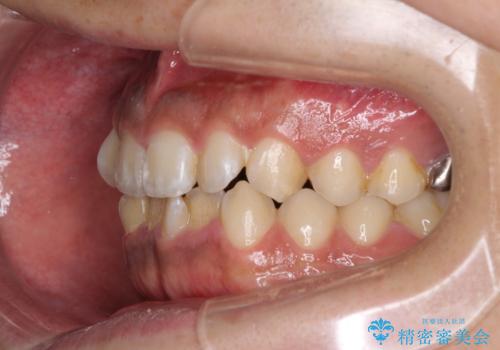

- 前歯のデコボコを気にして来院された患者様です。

前歯が90度近く捻れていたため、しっかりと治すことを考えるとワイヤー矯正の方がおすすめではありましたが、本人の希望によりインビザラインを用いて矯正治療を行うこととしました。

インビザラインは、十分な装着時間が達成されると前歯のデコボコをしっかりと改善できますが、1日の装着時間が20時間に達しなくなると、不十分な仕上がりとなるため、しっかりと装着するよう指示をしました。

途中2年強の来院がなく、改善されていたデコボコが元に戻ったり、装着時間が不足しており前歯のデコボコは十分に改善することはできませんでしたが、5年間の有効期限内で可能な限り歯列を整えることができました。